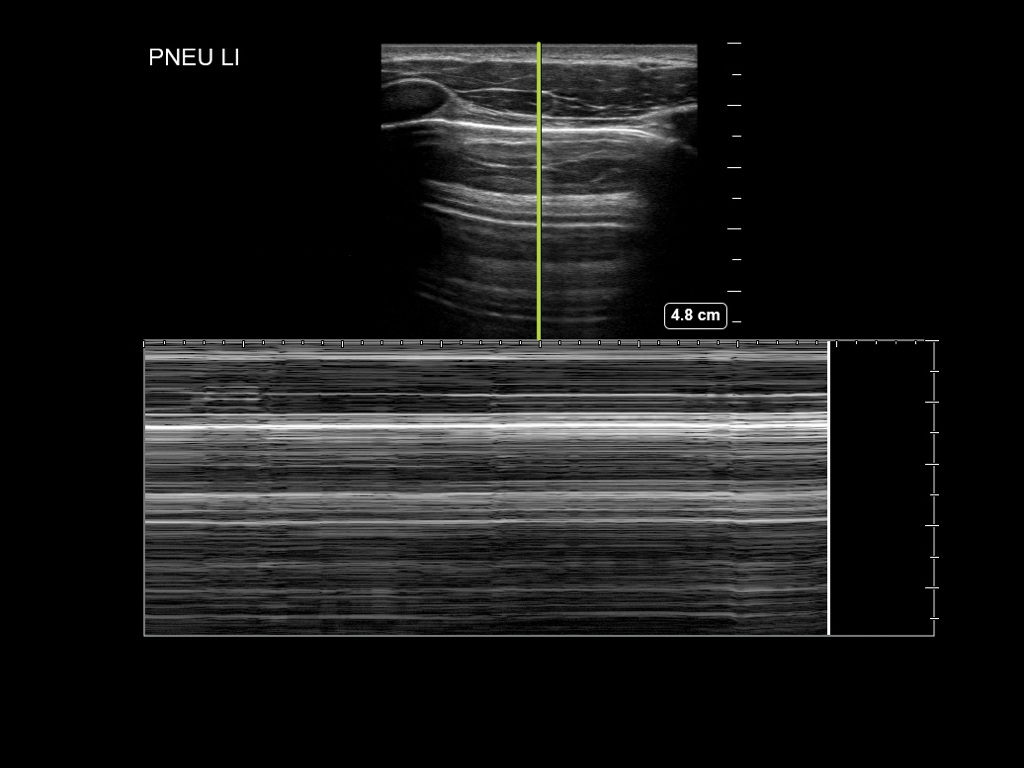

- Im M-Mode: ein Strahl wird durch das subkutane Gewebe, die Interkostalmuskulatur, Pleura und Lunge gelegt. Bei normalen Verhältnissen entsteht unterhalb der Pleuralinie ein granuliertes Muster, während im Bereich der Cutis, Subcutis und Interkostalmuskulatur ein lineares Muster entsteht („Seashore-Sign“). Bei Vorliegen eines Pneumothorax ist aufgrund der fehlenden Bewegung im Bereich der Pleuralinie ein durchgehend lineares Muster zu beobachten („Barcode-Sign“).